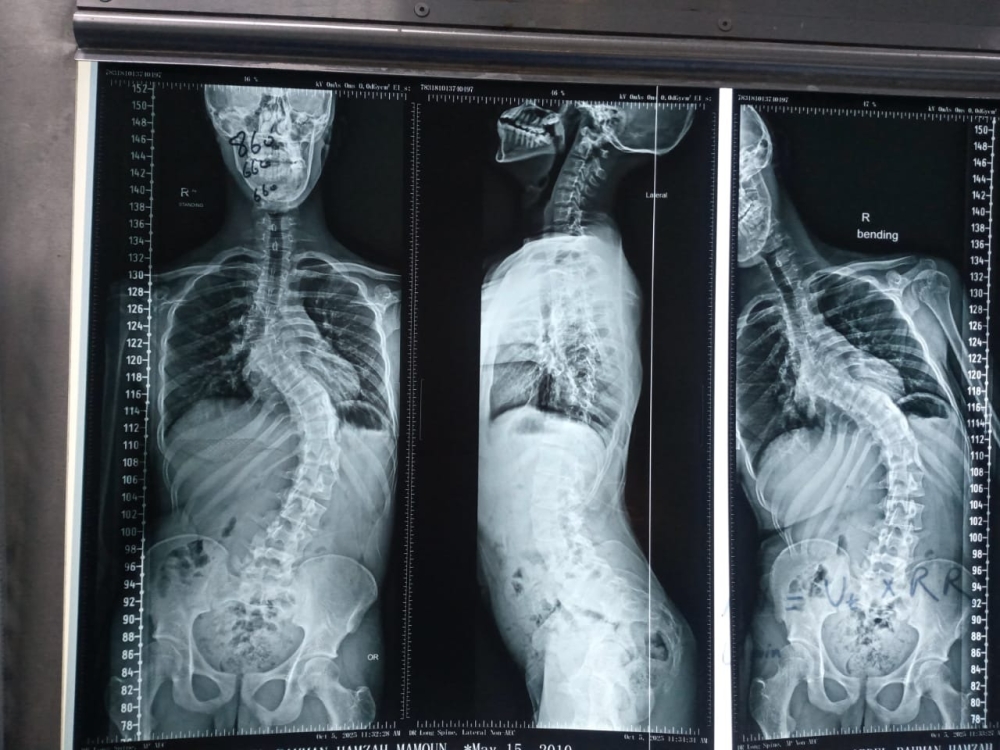

شهد قسم جراحة العمود الفقري في مستشفانا إنجازا طبيا مميزا تمثّل في إجراء تدخل جراحي معقّد لتصحيح جنف العمود الفقري لدى أحد المرضى الذين يعانون من تشوّه حاد في الفقرات.

وقد أُجريت العملية باستخدام جهاز الملاحة الجراحية المتقدّم، الذي أتاح دقةً عالية في التعامل مع التشوّهات البنيوية الشديدة، وسهّل توجيه الأدوات الجراحية ضمن المسار الآمن والمثالي. كما اشتملت العملية على إزالة أجزاء محددة من الأطراف الخلفية للفقرات لتحقيق التصحيح المطلوب واستعادة التوازن والمحاذاة الطبيعية للعمود الفقري.

كما تم تنفيذ هذا الإجراء الدقيق تحت نظام مراقبة الأعصاب المتواصل (Intraoperative Neuromonitoring) لضمان سلامة الوظائف العصبية على مدار مراحل العملية.